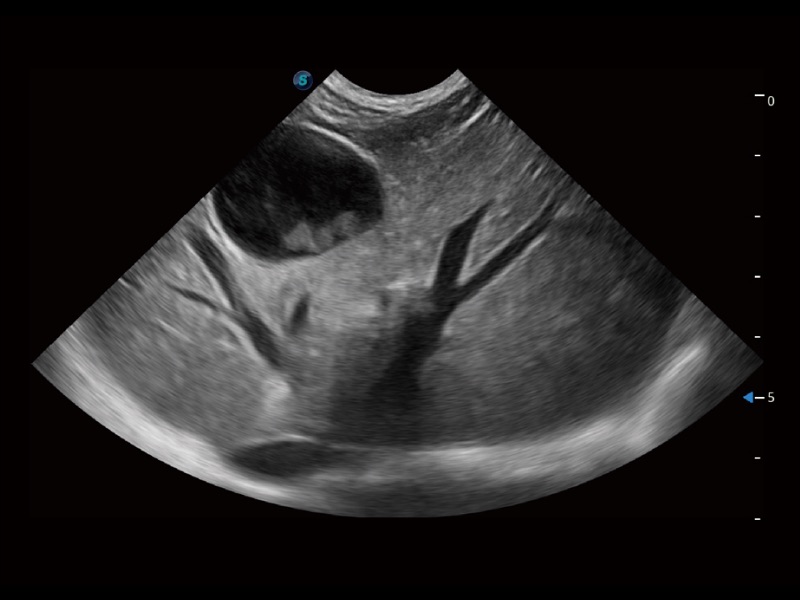

大型犬、马科、农场动物及大型异宠动物

通过创新的 Matrix E自适应滤波器和超长时间域算法,极大提升超低速微细血流的检出能力,同时更精准地滤除软组织和噪声信号,为兽用医生提供以往无法通过常规血流获得的疾病诊断信息。

为精细结构及组织边缘提供高清晰度的图像和更大的成像视野。帮助减轻医生的用眼疲劳,快速精准获得测量的数据。